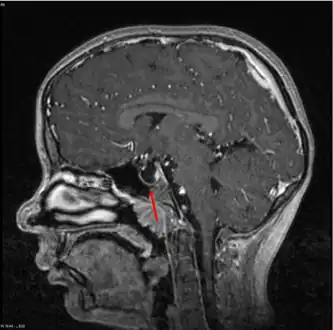

| MRI of Empty Sella | |

Empty sella- MRI Scan of the brain, sagittal T2-weighted

Empty sella in MRI